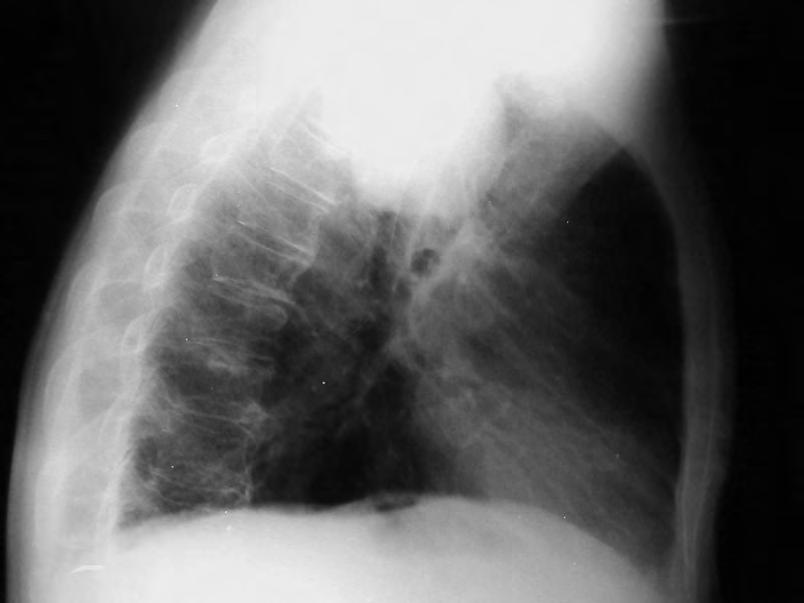

Expanzivní ložisko vCNS může být někdy způsobeno benigním patologickým procesem (abscesem, kavernomem, meningeomem), ale může jít také ometastázu známého nebo doposud ukrytého tumoru, viz obr. 1.4 a1.5. Do mozku často metastazují následující tumory: bronchogenní karcinom, obzvláště jeho malobuněčná varianta, karcinomy prsu aledvin. V80 %případů jsou tyto metastázy uloženy supratentoriálně.

Obr. 1.4 Miliární metastázy mozku bronchogenního karcinomu s okluzí aquaeduktu a hydrocefalem. MR zobrazení v koronárním řezu v T1 váženém čase po aplikaci kontrastní látky i.v. Bílá šipka ukazuje v tektu umístěnou metastázu blokující svou expanzí aquaedukt.

Metastázy mohou vCNS vytvořit jak solitární, tak ivícečetná ložiska, mohou však také infiltrovat meningy (bronchogenní karcinom, karcinomy prsu ižaludku).

Nález multiformního glioblastomu se při CT vyšetření zobrazuje jako hypodenzní ložisko s často vyjádřeným mass-efektem. Po nitrožilním podání kontrastní látky se uvíce než 90%nemocných zobrazuje hyperdenzní prstenec, tzv. ring sign Tento nález není typický jen pro glioblastom, ale je možno se sním setkat iumozkového abscesu. Podobně jako glioblastom může hypodenzní ložisko vCT obraze vytvořit rovněž metastatický nádor nebo infarkt mozku. Edém obklopující glioblastom je rozsáhlý amá nepravidelný prstovitý charakter. Po podání kontrastní látky se nasycení (enhancement) nevytvoří u60 %nízkostupňových astrocytomů, 30 %anaplastických astrocytomů, ale pouze

Obr. 1.5 Miliární metastázy mozku bronchogenního karcinomu s okluzí aquaeduktu a hydrocefalem. MR zobrazení v sagitálním řezu v T1 váženém čase po aplikaci kontrastní látky i.v. Bílá šipka ukazuje v tektu umístěnou metastázu blokující svou expanzí aquaedukt.

u6,5%glioblastomů. Platí, že čím vyšší je malignita, tím větší je imass-efekt.